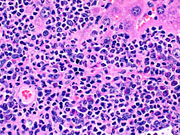

Another case of myelodysplasia. Numerous granulocytes with eosinophilic granular cytoplasm and a smaller number of mononuclear cells are visible in the high magnification view.